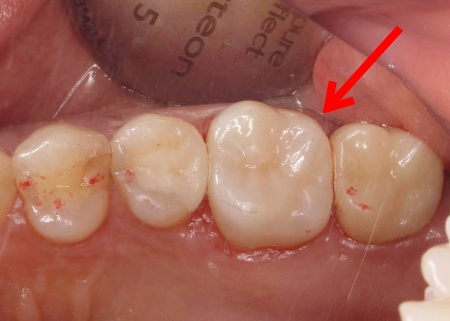

| 行ったご提案・治療内容 | 患者様は噛む力が非常に強く、その影響でエナメル質が割れてしまっています。 そこで詰め物の素材には、自費診療の白い素材「セラミック」の中でも、人工ダイヤモンドと呼ばれるほど強度があり、審美性にも優れている「ジルコニア」を選択しました。 すべての詰め物にジルコニアを用いるのが理想でしたが、ジルコニアは費用が高額です。 詰め物の形状には、歯の溝や一部を補う小さな詰め物「インレー」と、歯の噛む面を広範囲で覆う「アンレー」があります。 まずはメタルインレーをすべて外し、詰め物を装着するために歯の形を整え、型取りを行います。 |

治療後